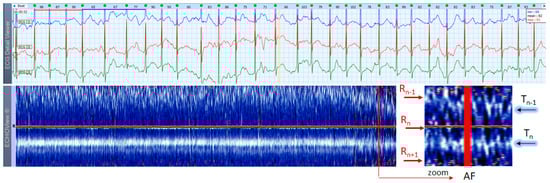

AF is the most common arrhythmia among humans (1 of 4 will have at least 1 episode of this arrhythmia in his/her life). This rhythm disorder and the less common AFL are usually not difficult to be recognized in standard 12-lead ECG strips if the ventricular rate is not too high and the fibrillation ‘f’ waves or flutter ‘F’ waves are visible in at least one lead. However, if HR is very high and irregularity of the rhythm, and fibrillations (in AF) or ‘saw-like’ fluctuations of the isoelectric line (in AFL) are not visible, it could be difficult to say what kind of arrhythmia the patient has. In addition, in many patients these arrhythmias are transitory and sought by Holter ECG/event recorders, which records frequently have a lot of artifacts due to physical activities and other factors. In such cases, ECHOView may help to recognize AF/AFL arrhythmias because they have a very characteristic pattern on the color map, as shown in Figure 13, Figure 14 and Figure 15. The notable behavior of AF is the absence of a P-wave band and scattered dots of R-wave peaks (Figure 13 and Figure 14), while AFL has presence of several F-wave bands and stable band of R-wave peaks (Figure 15). Beneficially, these ECHOView maps sufficiently differ from the patterns of other high-rate arrhythmia, such as SINT (Figure 6, Figure 7 and Figure 8), SVA (Figure 9) and PSVT (Figure 10, Figure 11 and Figure 12).

ECHOView interpretation turned out to be very important for some of our patients with episodes of supraventricular rhythm disorders such as SINT, SVT, AF and AFL. These arrhythmias are very common among the general population, affecting both younger and older people, with or without underlying cardiac injury [1,2,3,4,5,6,7]. A lot of non-cardiac conditions such as thyroid dysfunction, chronic lung diseases, electrolyte disturbances, infections (including COVID-19), etc. could also ‘unlock’ SVAs [1,2,8]. The diagnosis is based mostly on non-invasive ECG methods, mainly standard 12-lead ECG and 24–72 h Holter ECG monitoring [1,2,3,4,5,6,7,8,9,10]. Standard 12-lead ECG records are obtained in rest and their quality is usually much better than Holter ECG records, but conventional ECGs are not the ideal tool for diagnosing arrhythmias. They present time frames of about 10–20 s and many patients with SVAs could be missed because arrhythmias are often transitory [1,2,3,4,5,8]. For this reason, diagnosis is usually obtained by Holter ECG monitoring or event recorders [1,2,3]. However, most of these devices record less number of channels (1 to 3) in which P-waves of the normal sinus rhythm may not be demonstrated [1,2,3,4,5,6]. In addition, external factors such as movements, posture, skin contact of the electrodes, etc. may exert significant influence on the quality of the records and the morphology of ECG components, thus making the detection of P-waves even more difficult [1,8,17]. One of the most common ECG challenges is the differentiation of a high-rate sinus tachycardia from other SVTs (AVNRT, AVRT, focal AT) and sometimes from high-rate AF/AFL. Physical activities, emotions, panic attacks, pain/severe discomfort, febrility, etc. may cause expressed sinus tachycardia with complaints indistinguishable from a true tachyarrhythmia [3,5,9]. The ECG leads to shortening of the RR intervals, the impossibility of recognizing regularity/irregularity of the rhythm, and identifying/distinguishing the normal sinus P-wave from pathological P-waves of AT, F waves of AFL and f-waves of AF could make diagnosis uncertain, particularly if the patient has already had arrhythmias or risk factors for the development of them [5,7,9]. In this article we present several cases in which patient’s complaints and the Holter ECG records required differentiation between SINT, SVT and AF/AFL. In our cases, ECHOView facilitated the accurate diagnosis clearly disclosing the P-wave in SINT (Figure 6, Figure 7 and Figure 8) and the pathological atrial excitations in cases of true tachyarrhythmias SVT (Figure 10, Figure 11, Figure 12 and Figure 16), AF (Figure 13, Figure 14 and Figure 16) and AFL (Figure 15 and Figure 16) but also the contrastive ventricular pattern of NSVT. As the prognostic significance and therapeutic approach to arrhythmias can vary greatly [40], such as the need for oral anticoagulation in AF/AFL [1,2], the advanced perspective of ECHOView is an important tool to improve risk assessment and therapeutic decision-making.

4.3. ECHOView: Summary of the Principles of Imaging

The color-coded ECG amplitudes of sequential beats produce an intuitive trace of different intervals (PnRn, RnTn, Rn−1Rn, RnRn+1, etc.) in a visible image (width × height = 1740 beats × 1500 ms) within one ECHOView page. Without a specific measurement, this visual effect resembles the rendering of one-dimensional time trends of automatically measured ECG intervals. These trends show stable PnRn and RnTn intervals during the NSR part of the examples in Figure 4, Figure 5, Figure 6, Figure 7, Figure 8, Figure 9, Figure 10, Figure 11 and Figure 12. The trends are also informative for the RR-intervals (Rn−1Rn, RnRn+1) on a beat-by-beat basis that is helpful for identifying long-term HR changes in high-rate SINT (Figure 6, Figure 7 and Figure 8) and AFL (Figure 15), as well as rhythm, transitions NSR→ paroxysmal SVA (Figure 9), NSR→PSVT (Figure 10, Figure 11 and Figure 12), NSR→NSVT (Figure 10, Figure 11 and Figure 12), and AF→AFL→ST (Figure 16).